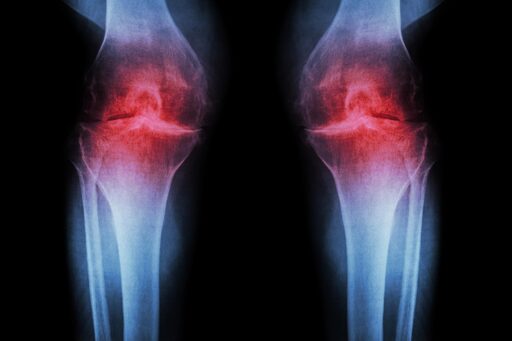

Published in November 2025, and the research was in mice and, “seems to suggest” that it could lead to regeneration of tissues in the knee. It is phenomenal, but far from being usable in an everyday medical setting yet…

https://med.stanford.edu/news/all-news/2025/11/joint-cartilage-aging.html